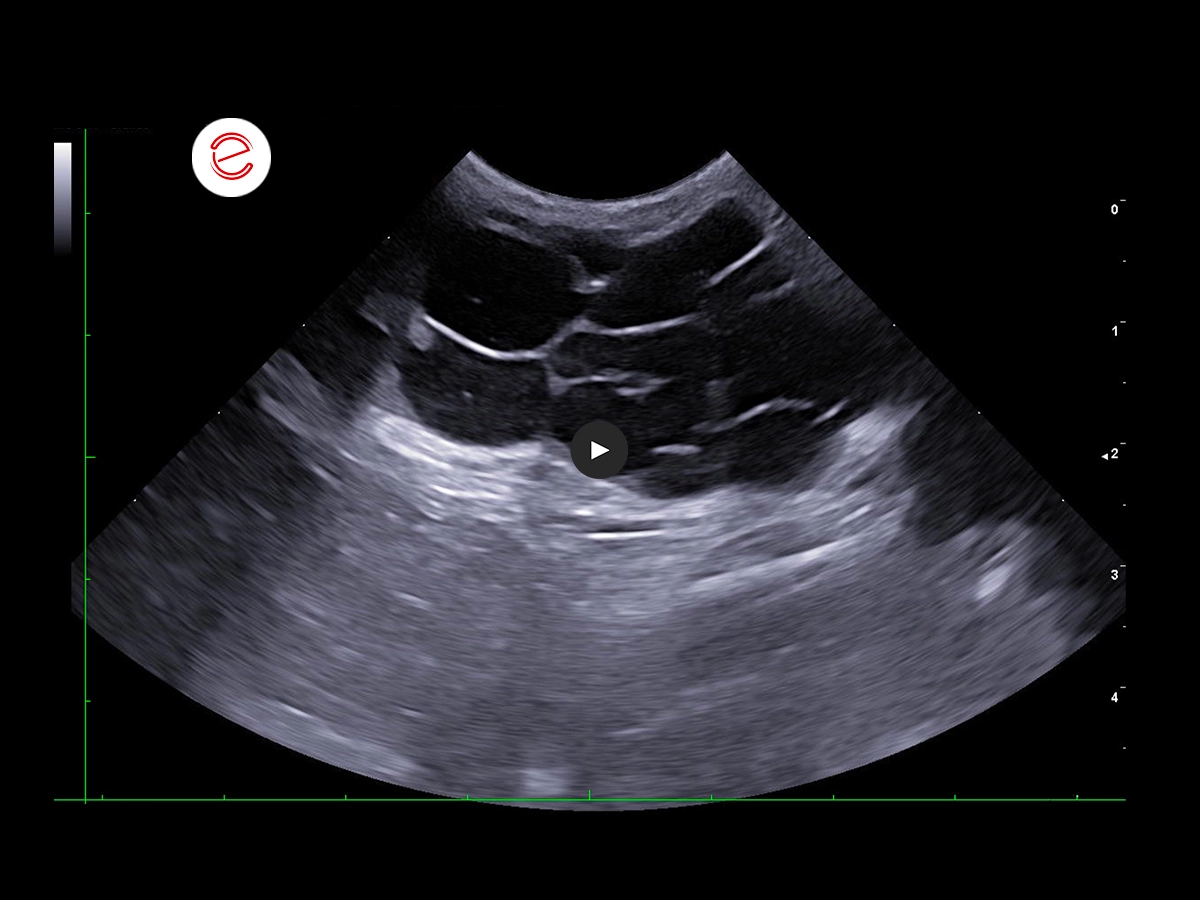

A multilobulated subcutaneous lesion consisting of multiple anechoic cavities with thin hyperechoic walls was observed in the right inguinal region, measuring up to 1.5 cm in diameter, and extending within the subcutaneous tissue in a cranio-caudal direction for approximately 7 cm.